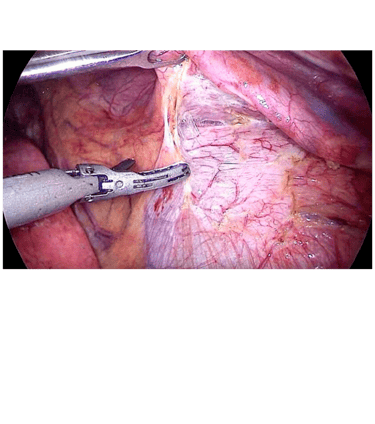

Terapia Híbrida percutanea, endovascular y quirúrgica

Terapia multidisciplinaria, individualizamos al paciente, para otorgar el angioacceso que mejor se ajuste a sus características.

Manejo quirúrgico para angioaccesos definitivos

Nos especializamos en la colocación de accesos vasculares intra auriculares por cirugía de mínima invasión videasistida y creación de neo conductos con injertos sintéticos